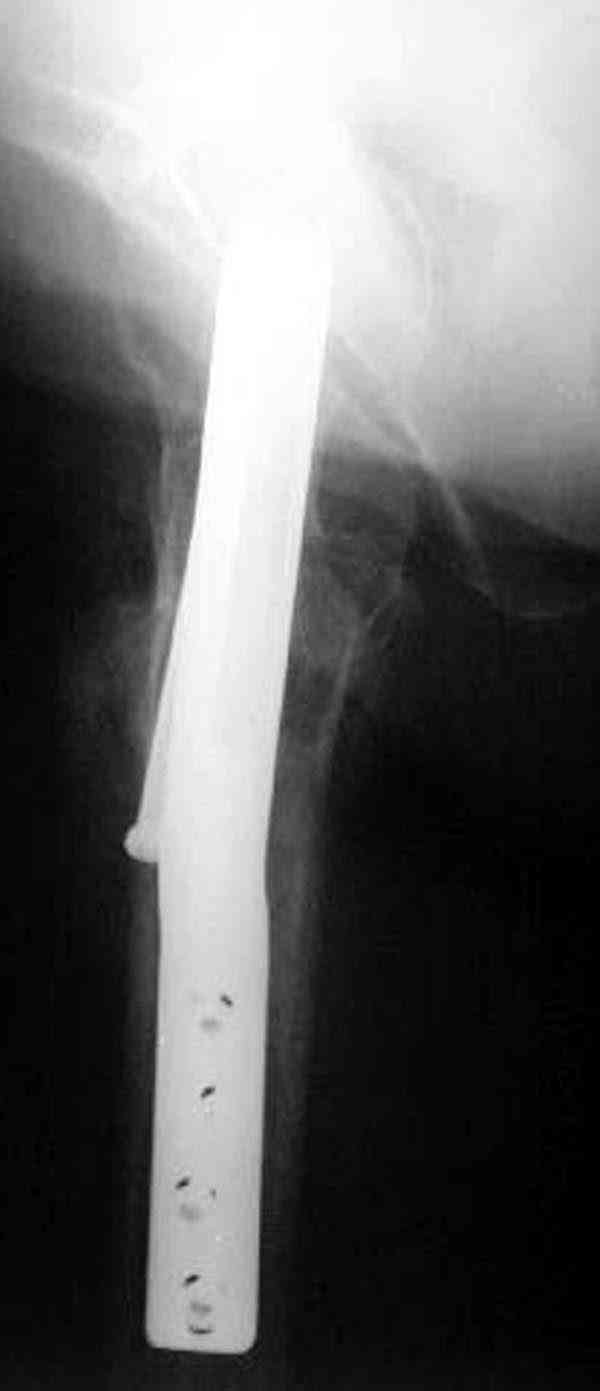

Здесь случай перелома из-за ослабления латерального кортекса через 3 недели после операции на шейке. Шурупы были установлены под большим углом, слабый латеральный кортекс не выдержал нагрузку.

Предлагая методику армирования, мы рассматривали вероятность ослабления кортикального слоя в месте проведения имплантата. В перспективе, эта проблема должна быть решена формой имплантата, путем добавления к винту диафизарной накладки длиной 6-8 см, через проксимальное отверстие которой будет введен канюлированный винт, в дистальной отверстие введен монокортикальный и лучше блокируемый винт диаметром не более 3,5 мм.